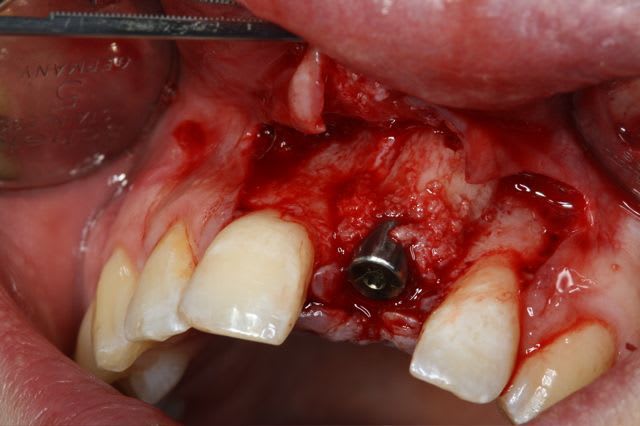

dépose des vis et pose de l'implant à 5mois1/2 avec un cj roulé et mise en place de la vis de cica,

nobel effectivement: RP Replace Groovy 4*13

Non pas speedy mais straight: apex moins agressif et implant moins compressif

J'ai eu beaucoup de craterisation avec le speedy ( surtout sur des sites anciens ) et sur une greffe je préfère la mise en place plus douce du straight pour ne pas risquer de 'décoller' le greffon cortical